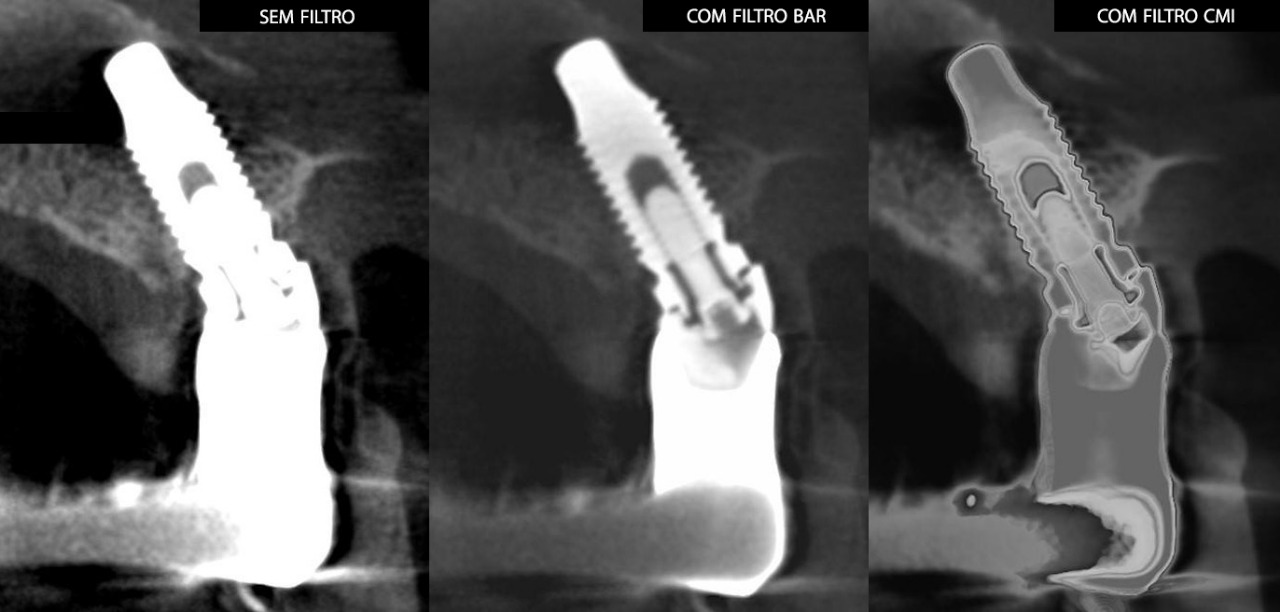

A empresa criou um sistema de radiologia odontológica que proporciona imagens realistas, oferecendo um nível de detalhamento profundo, permitindo a interpretação correta, eficaz e rápida do profissional. “O resultado final é surpreendente. Incrível. Já temos feedbacks extremamente positivos de profissionais renomados em todo mundo”, comenta do criador da empresa, Roney Rocha.

Entre os produtos oferecidos pela CDT Software é o E-VOL DX, reconhecido por pesquisas acadêmicas nacionais e internacionais de odontologia, possibilita imagens mais nítidas e com maior riqueza de detalhes! “O e-Vol DX é um software que supre demanda dos tradicionais aparelhos de radiologia. Compatível com os principais equipamentos do mercado, ele é composto por filtros e ferramentas que transformarão seus laudos”, ressalta.

Além disso, o e-Vol DX está em constante atualização para atender e antecipar-se às demandas dos profissionais da área de radiologia odontológica. Por isso, é um investimento seguro e eficaz e que não estará defasado. Com todos os recursos que garantem obter as melhores imagens de seu tomógrafo, o e-Vol DX possibilita otimizar o tempo de produção com o uso de ferramentas exclusivas.